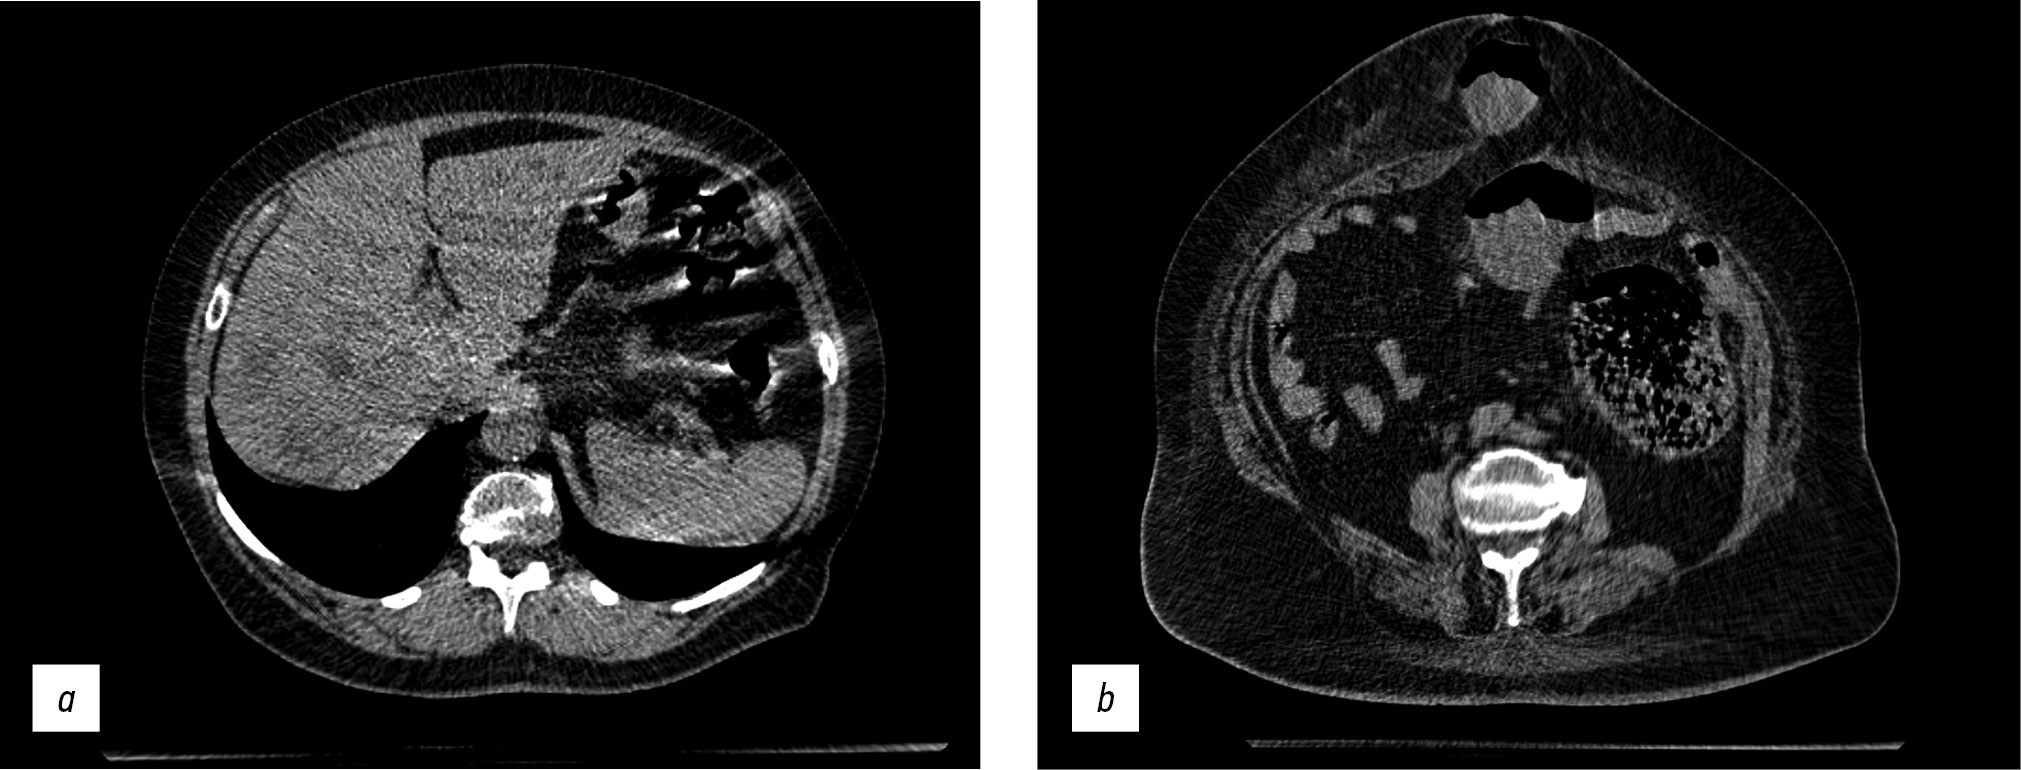

Abdomen CT was used to assess acute abdominal problems, such as suspected intestinal blockage, and detect free liquid or gas (Fig. 9).

Fig. 9. Axial computed tomographic images of the abdomen: (a) CT image of multiple hypodense lesions of both liver lobes, helical artifacts, and gas interface artifacts in the intestinal area and (b) CT image of a strangulated umbilical hernia.

Artifacts were also identified during abdomen CT at the point of contact of various density media, such as intestine gas and surrounding soft tissue (gas-interface artifact) and helical scanning artifacts.

The scanning parameters (Table 1) enable the acquisition of images of sufficient quality for the diagnosis of abdominal and retroperitoneal disorders (liver steatosis, gallstone disease, adrenal hyperplasia and incidentaloma, kidney cysts and urolithiasis, focal liver lesions, and other conditions).